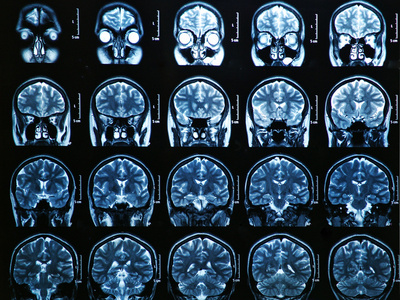

侧脑室磁共振成像大脑扫描照片